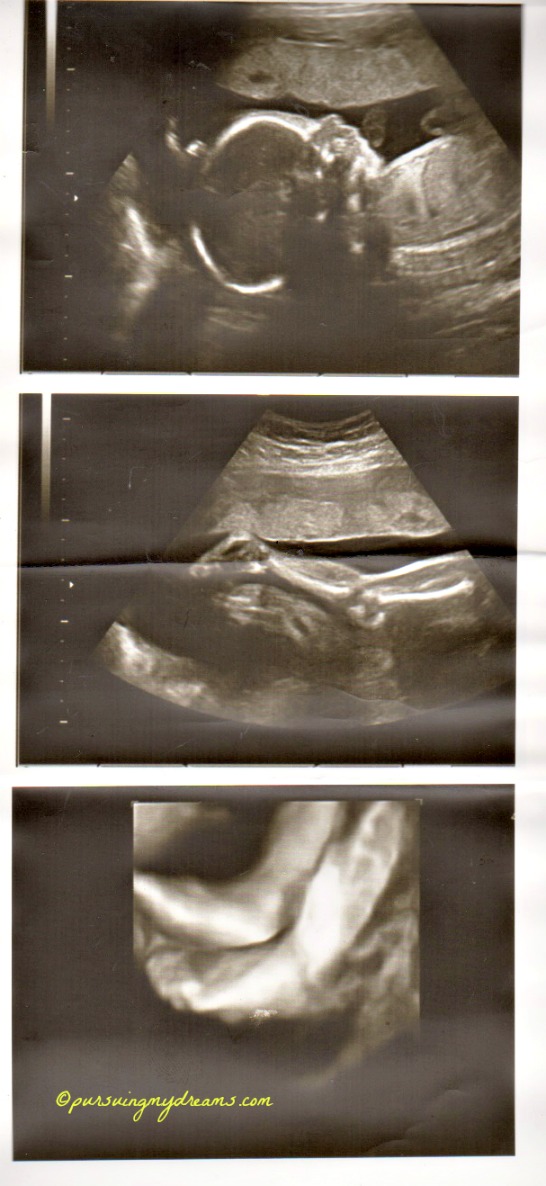

Sebagai penutup saya sertakan foto hasil usg anakku. Ini usg saat usia kehamilan 25 minggu. Dilakukan di kliknik Mannheim. Setelah itu sampai saat ini dokter tidak pernah melakukan pemeriksaan usg lagi karena semuanya baik-baik saja. Jadi hanya diperiksa posisi kandungan.

yang 2x karena aku ada pemeriksaan di klinik yg lebih besar Cha trus dikasih print out USG nya, klo di dokter biasa cuma 2x ga dikasih print out usgnya 😥 .

Mending mbak 3x disini kl hamilnya normal, mksdku gak melalui IVF kaya’nya cm 2x deh USG nya udh gt ya yang 2D itu doank, itu 4D kan mbak yah?? 36 mgg gak terasa ntar lagi bertiga deh kaliaaaan… Semoga sehat dan lancar ampe lairannya ntar ya mbak :*

Aku sdh 36 minggu nih. USG cuma 3 kali 🙁 pelit dokternya pdhl tiap kali ke dokter aku semangat pengen lihat si kecil kan.

Iya bang keliatan jelas, padahal itu masih 25 minggu. Ga tau saya usg apa namanya hehehe.

Hidung anakku ngikut aku Ndang alias pesek, dokternya bilang gitu 😆 .

wah… udah kelihatan jelas. itu pake uSG 3 dimensi yah? mirip sama buku ….. ah lupa judulnya… isinya seh kebanyakan foto perkembangan janin di setiap minggunya